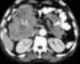

Solid pancreatic mass

Pancreatic mass